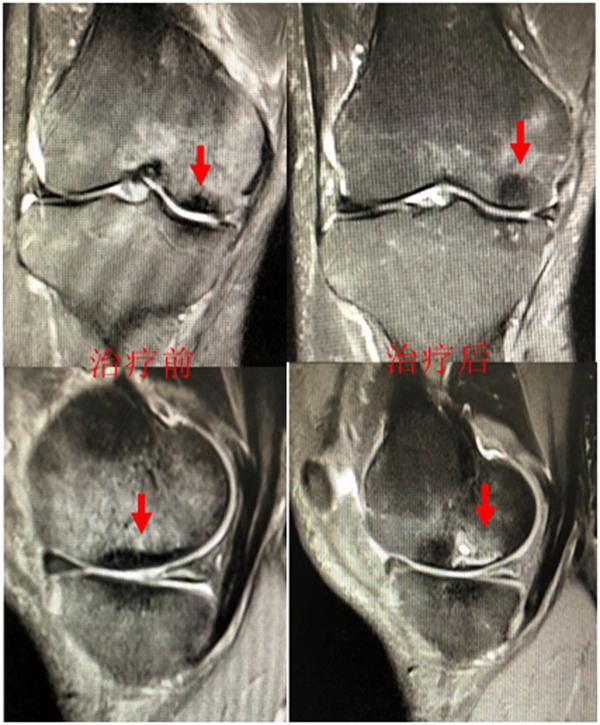

病例:女,65岁,主诉左膝关节内侧疼痛2月余。2017年11月X光未见左膝骨质异常。MR见股骨内侧髁骨坏死,半月板相对突出百分比(RPE)28.3%,合并内侧半月板后根部撕裂,矢状位病变区域前后径为11.67mm,关节线会聚角2.68°

予消炎止痛药物口服、静滴唑来膦酸钠注射液,避免负重6周,后改部分负重,12周后全负重。

2018年2月复查MR见骨髓水肿明显吸收,坏死灶边界清晰,半月板相对突出百分比(RPE)28.92%

2018年6月复查MR见骨髓水肿基本完全吸收,坏死区修复良好,半月板相对突出百分比(RPE)38.54%,患者临床症状消失。

提示坏死好转了,但半月板突出进展了,膝关节的退变加重了。

病例1:女,65岁,主诉右膝关节内侧疼痛1周。2018年1月X光未见右膝骨质异常,MR检查见股骨内侧髁骨坏死,半月板相对突出百分比(RPE)28.99%,关节线会聚角1.4°。

予切开行克氏针钻孔减压,口服消炎止痛药物、钙剂及骨化三醇,不负重6周,后改部分负重至3个月。2018年4月复查MR见骨髓水肿基本完全吸收,坏死区局限并修复良好,半月板相对突出百分比(RPE)32.08%,患者临床症状消失。

保守治疗4个月后复查

保守治疗后效果欠佳,坏死范围扩大、塌陷